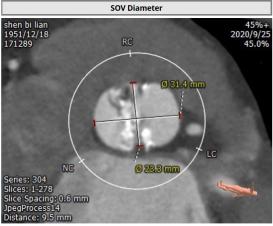

CT:

主动脉瓣Type 0型二叶瓣,瓣叶瓣缘结节样增厚伴中度钙化,开放受限。冠脉高度可。法式窦结构可,心脏角度约52°,左室较小,升主动脉未见明显扩张,右股动脉直径大于5.5mm,可作为主入路。患者为中度钙化的,重度主动脉瓣狭窄,呈鱼嘴型,结合主动脉根部结构,考虑植入Sapien 3瓣膜。

主动脉瓣环

左室流出道

法式窦

窦管结合部

升主动脉

左冠高度

右冠高度

钙化情况

心脏角度

入路情况